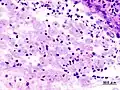

Amoebae in a colon biopsy from a case of amoebic dysentery. -

Immunohistochemical staining of trophozoites (brown) using specific anti–Entamoeba histolytica macrophage migration inhibitory factor antibodies in a patient with amoebic colitis.